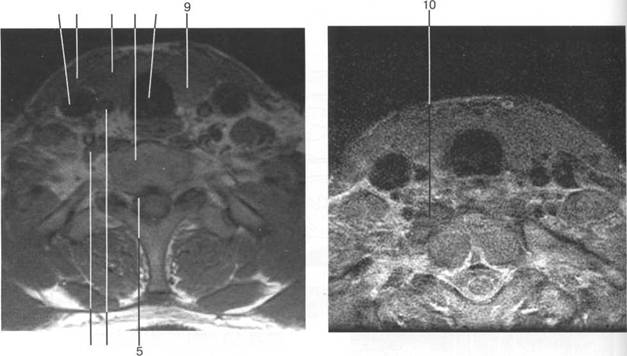

lig. thyrohyoideum;

a. carotis dextra; a. carotis sinistra; cartilago thy-roidea; a. thyroidea superior; v. thyroidea superior; v. jugularis interna; a. subclavia dextra; v. subclavia dextra; a. subclavia sinistra; v. thyroidea inferior; v. thyroidea superior im-par; trancusbrachiocephalicus; v. brachiocephalica dextra; v. brachiocephalica sinister; a. subclavia; a. pulmonalis;

m. longus coli; 1 sternocleidomastoideus; sternohyoideus; sterno-thiroideus; thyreoideus; platysma; fascia coli profunda; m. longus capitis; m. scalenius anterior; m scalenius medius; m. scalenius posterior; a. facialis; a. lingualis; a. thyreoideus superior; cartilago cricoidea; cartilago thiroidea.